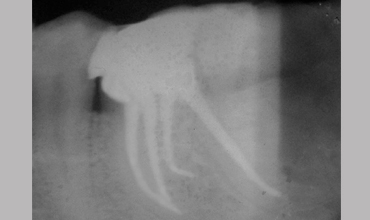

Management Of Radix Entomolaris In Mandibular First Molar